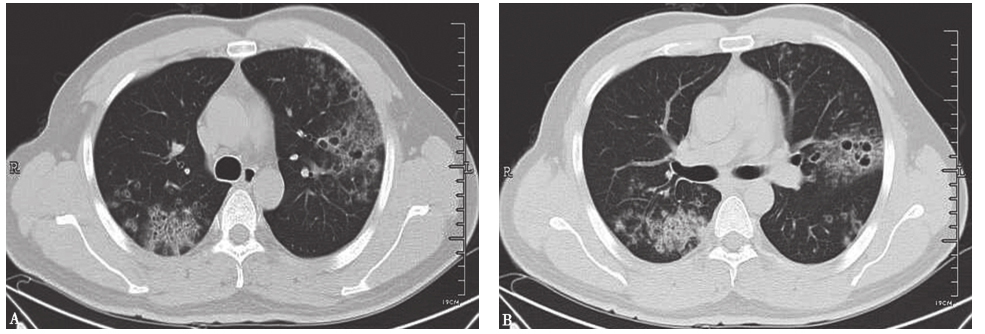

在感染性疾病中,首先要排除肺部真菌感染及肺部化脓性细菌感染。肺部真菌感染患者往往有免疫力下降病史,并伴有发热、咳嗽等症状,辅助检查可发现血常规、C反应蛋白升高,胸部影像学表现可见短期内动态变化(图2)。肺化脓性细菌感染表现为双肺多发空洞,有时空腔内合并小液平,可合并胸腔积液(图3)。本例患者无明显发热等全身症状,病史不符合急性感染性疾病特征,但仍须进一步完善感染标志物等检查以明确病情。

图2侵袭性肺曲霉菌病胸部CT表现

男患者性,53岁,发热、咯血1周,伴呼吸困难,诊断为侵袭性肺曲霉菌病。胸部CT初期表现为沿支气管分布的粟粒样结节(A);1周后表现为多发沿支气管分布的空洞,有中心性支气管扩张(B)

图3血源性金黄色葡萄球菌肺炎胸部CT表现

胸部CT可见双肺多发结节空洞性改变,部分空洞伴液平,病灶周围可见渗出表现